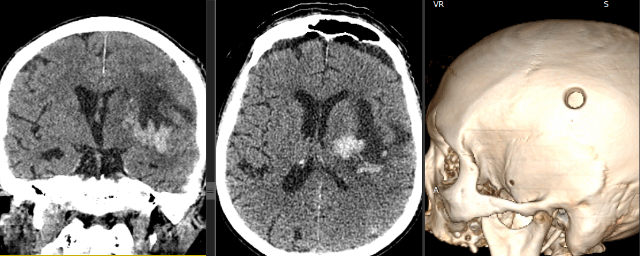

Инсульт удаление гематомы

Инсульт удаление гематомы 108 фотографий